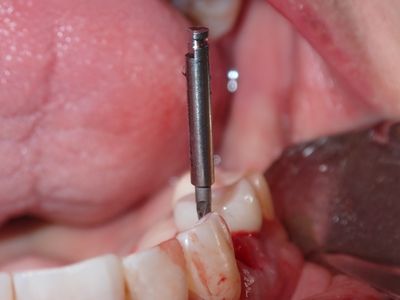

relatively straight forward immediate placement, loss of labial plate at apex of 3mm, implant placed well away from that site, grafted that region from internal of socket with membrane and bone prior to placing implant. additional bone placed post implant placement .